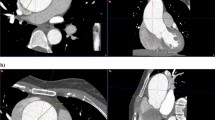

Images were reviewed on (Singovia; Medical Systems, Siemens, Erlangen, Germany). The short axis of the aortic root was determined on the best systolic phase by perpendicular lines on two orthogonal planes of the aorta, Fig. 1. The aortic root rotation (in plane) was defined as any clockwise rotation of the aortic root about the centerline of the aortic root. To measure the angle of the aortic root rotation, using a true short-axis view of the aortic valve a line connecting the mid-point of the non-coronary sinus to the interleaflet anterior commissure between the coronary sinuses, as defined in a previous publication4, was drawn and its angle with the plane of the interatrial septum (IAS) was measured. The plane of IAS was drawn between the anterior and posterior insertion points of IAS in the left atrium, Fig. 2.

Proximal MPA diameter was measured on the sagittal plane, the diameter was taken at the widest part before MPA bifurcation during the systole phase. Proximal MPA diameter was indexed for body surface area, Fig. 3.